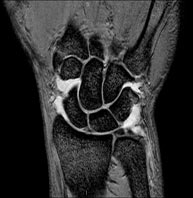

Exploración para el estudio de lesiones en tendones, músculos y nervios periféricos. Tiene una duración aproximada de 18 minutos. No emplea radiación ionizante. - RM Muñeca / carpo

Exploración para el estudio de lesiones en tendones músculos y articulación. Muy útil para la valoración de pequeñas fracturas inadvertidas, lesiones de ligamentos, y procesos inflamatorios y degenerativos (artritis y artrosis). Tiene una duración aproximada de 20 minutos. No emplea radiación ionizante. - RM Mano / dedos

Exploración para el estudio de las lesiones en pequeñas estructuras anatómicas de la articulación que suelen lesionarse en pacientes que sufren luxación o inestabilidad crónica. El estudio viene precedido por una inyección de contraste en el interior de la articulación, realizada bajo control de rayos X. La duración global de los dos procedimientos es de 50 minutos. - Artro-RM Muñeca

Exploración para el estudio de las lesiones en pequeñas estructuras anatómicas de sus articulaciones tales como ligamentos y cartílago. El estudio viene precedido por una inyección de contraste en el interior de una de las articulaciones, realizada bajo control de rayos X. La duración global de los dos procedimientos es de 50 minutos. - Artro-RM Cadera